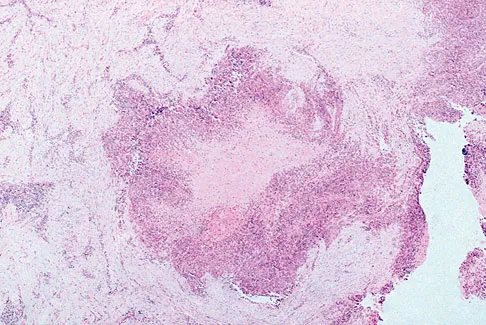

Figures 12a through 12e show the radiograph, MRI scans, and biopsy specimens of a 17-year-old boy. What is the most likely diagnosis?

Explanation

The images show an epiphyseal lesion. The MRI scan shows extensive bone edema surrounding the lesion, consistent with chondroblastoma. Histology shows polygonal chondroblasts in a cobblestone-like pattern and areas of calcification consistent with chondroblastoma. Although some giant cells are seen, the age of the patient and the polygonal chondroblasts differentiate this lesion from giant cell tumor. Clear cell chondrosarcoma is an epiphyseal lesion that occurs in an older population, and the cells have clear cytoplasm. This lesion is not producing bone on imaging or histologic specimen, eliminating osteosarcoma. Tuberculous septic arthritis can be an epiphyseal lesion, but granulomas would be seen on histology. Menendez LR (ed): Orthopaedic Knowledge Update: Musculoskeletal Tumors. Rosemont, IL, American Academy of Orthopaedic Surgeons, 2002, pp 103-111.